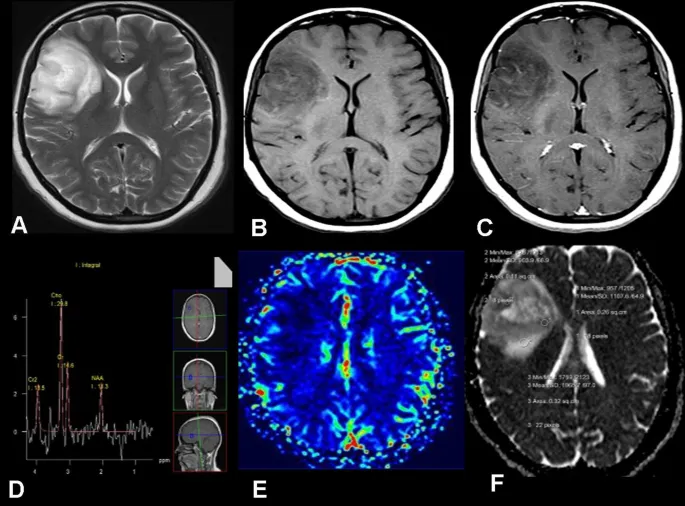

ADC Interpretation - Decoding Diffusion's Dance

- Apparent Diffusion Coefficient (ADC) map: Quantifies water molecule mobility, derived from DWI.

- Low ADC (Dark on map): True restricted diffusion.

- Cytotoxic edema (e.g., acute stroke, cellular tumors).

- High ADC (Bright on map): Facilitated diffusion.

- Vasogenic edema, cysts, chronic infarcts.

- T2 Shine-through vs. True Restriction:

- True Restriction: DWI ↑, ADC ↓ (e.g., acute stroke).

- T2 Shine-through: DWI ↑, ADC ↑ (lesion bright on T2, no true restriction).

⭐ In acute stroke, DWI shows high signal and ADC shows low signal due to restricted water diffusion in cytotoxic edema.

Perfusion Techniques - Blood Flow Blueprint

Assesses blood delivery to tissues, crucial for evaluating tissue viability.

- Dynamic Susceptibility Contrast (DSC-MRI):

- Principle: Bolus tracking of T2* contrast agent (e.g., Gadolinium) causing signal drop.

- Parameters: Cerebral Blood Volume (CBV), Cerebral Blood Flow (CBF), Mean Transit Time (MTT), Time To Peak (TTP).

Clinical Perfusion - Stroke & Tumor Power

- Acute Stroke:

- Core (DWI lesion) vs. Penumbra (PWI/DWI mismatch = salvageable tissue).

- Guides reperfusion therapy decisions.

- Brain Tumors:

- Grading: ↑ Cerebral Blood Volume (CBV) suggests high-grade glioma.

- Distinguishes tumor (high CBV) from non-neoplastic lesions (e.g., abscess, tumefactive MS often show lower CBV).